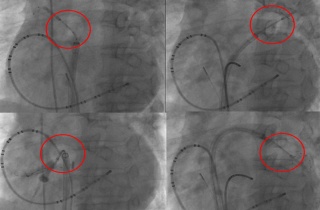

°Ç±¹´ëº´¿ø, ½É¹æ¼¼µ¿ ³Ã°¢ µµÀÚ ÀýÁ¦¼ú µµÀÔ

[µ¥Àϸ®¸Þµð ¹ÚÁ¤¿¬ ±âÀÚ] °Ç±¹´ëº´¿øÀº ½É¹æ¼¼µ¿ Ä¡·á¹ýÀÎ ³Ã°¢ µµÀÚ ÀýÁ¦¼úÀ» ½ÃÀÛÇß´Ù°í 6ÀÏ ¹àÇû´Ù. ½É¹æ¼¼µ¿Àº Á½ɽǰú2020-02-06 16:18:51